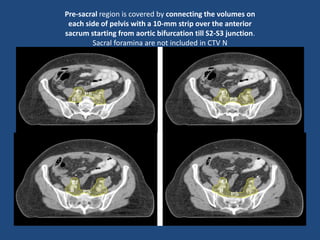

Pre-sacral region is covered by connecting the volumes on

each side of pelvis with a 10-mm strip over the anterior

sacrum starting from aortic bifurcation till S2-S3 junction.

Sacral foramina are not included in CTV N